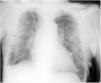

Paciente de 86 años de edad que ingresa en nuestra unidad tras realización de intervencionismo percutáneo urgente por infarto agudo de miocardio con elevación del ST de cara anterior con implante de 2 stents farmacológicos en DA y 1.a diagonal. A su ingreso en situación hemodinámica y respiratoria estable con saturación de oxigeno por pulsioximetría del 93% sin aporte de oxígeno. Se le realiza radiografía (Rx) de tórax en supino en la que se observan 2 líneas sugerentes de neumotórax bilateral (fig. 1, flechas) que dejan de visualizarse en lóbulos superiores (fig. 1, puntas de flecha). Para descartar el neumotórax bilateral se realiza ecografía torácica bilateral en la que se observa «sliding» pleural e imagen en modo M de «orilla del mar» o «seashore sign» (fig. 2). En una Rx realizada después, en semisedestación, solo se observa una pequeña línea basal derecha (fig. 3), estableciéndose el diagnóstico de falso neumotórax bilateral secundario a pliegue cutáneo.